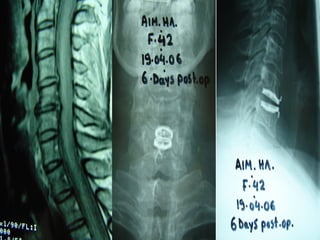

Infections

Cervical spine

Cervical Epidural abscess

•Anterior vertebrectomies

•Evacuation of the epidural abcess

•Cage and stabilization with plate and screws

•Posterior stabilization